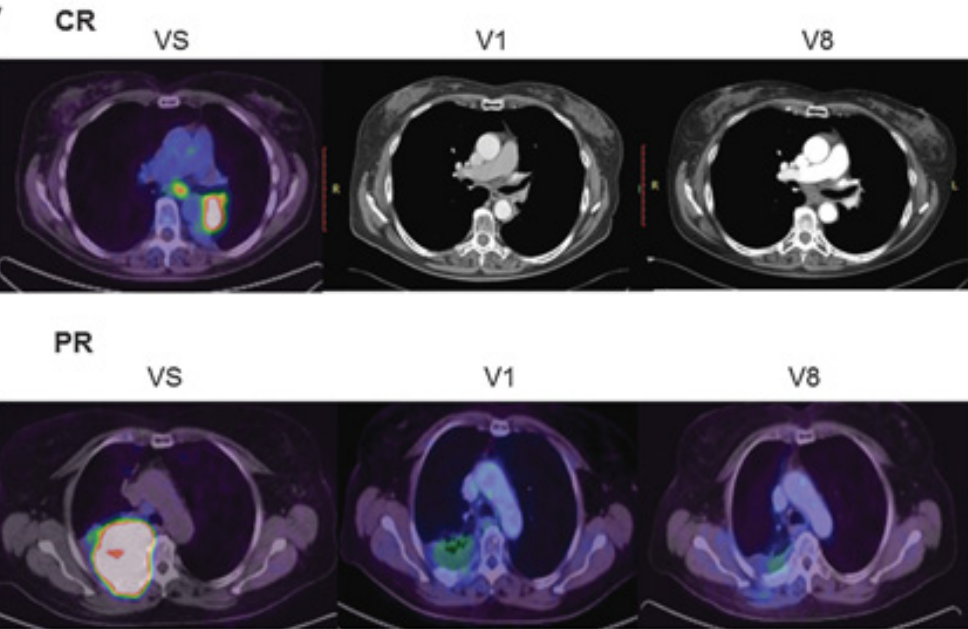

近日,《Neuro-Oncology》在线全文发表了埃克替尼联合阿美替尼一线治疗EGFR突变伴脑转移非小细胞肺癌患者的疗效与安全性的一项I/II期临床研究的研究结果。